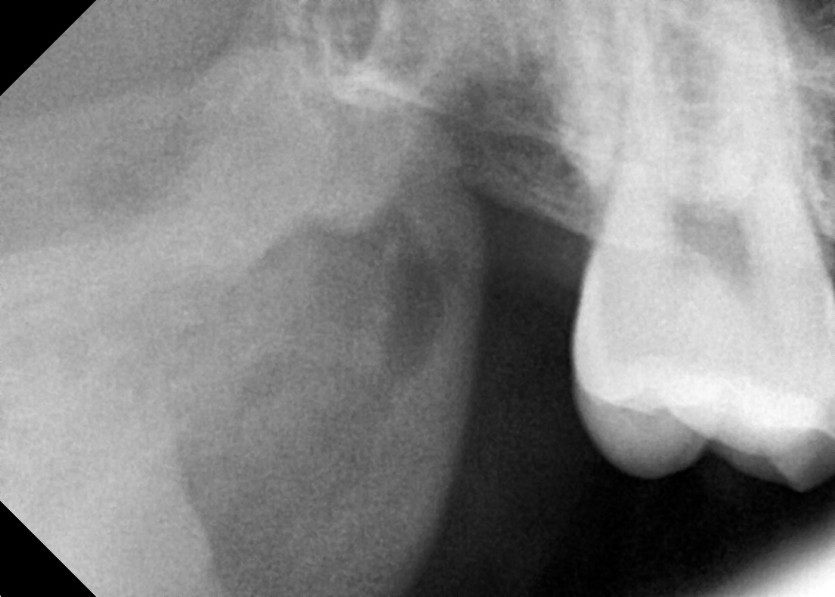

#48 사랑니 발치

구강외과 전문의가 당일 발치했습니다.